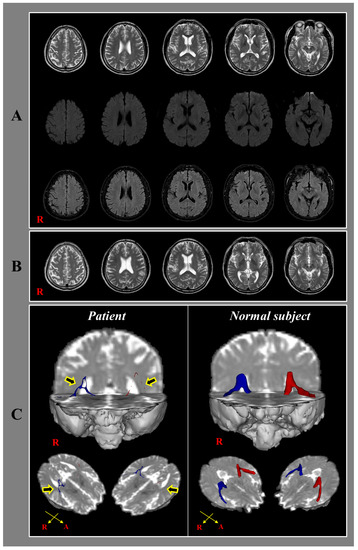

We report on a patient with tinnitus who showed injury of auditory radiation following whiplash injury, demonstrated by diffusion tensor tractography (DTT). A 48-year-old male patient suffered from a car crash resulting in flexion-hyperextension injury of his head after being hit from behind [...] Read more.

We report on a patient with tinnitus who showed injury of auditory radiation following whiplash injury, demonstrated by diffusion tensor tractography (DTT). A 48-year-old male patient suffered from a car crash resulting in flexion-hyperextension injury of his head after being hit from behind by a moving car while waiting at a signal while driving a car. Three days after the car crash, he began to feel tinnitus in both ears and his tinnitus became aggravated with the passage of time. No specific lesion was observed on a conventional brain MRI performed two weeks after the car crash. Although he visited several hospitals, the precise cause of his tinnitus was not detected. Two years after the car crash, he underwent evaluation for his tinnitus at the ear, nose and throat department of a university hospital. The pure tone audiometry was evaluated in a sound-proof room to screen his hearing status for the frequencies of 250–8000 Hz and no specific abnormality was detected. Although he was also tested for speech audiometry, there was also no specific abnormality. In order to assess his tinnitus, a tinnitogram was conducted to evaluate the frequency content and the loudness. His tinnitus was characterized at an intensity of 40 dB and a frequency of 4000 Hz. However, no abnormality was observed in either ear on physical examination. On DTT, the auditory radiation showed severe narrowing and tearing in both hemispheres. To summarize, neural injury of the auditory radiation was demonstrated in a patient with tinnitus following whiplash injury, using DTT. Full article